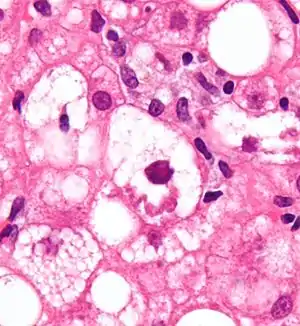

| Micrograph showing a Mallory body, a histopathologic finding associated with alcoholic hepatitis. H&E stain. | |

- Mallory's hyaline body – a condition where pre-keratin filaments accumulate in hepatocytes. This sign is not limited to alcoholic liver disease, but is often characteristic.[5]